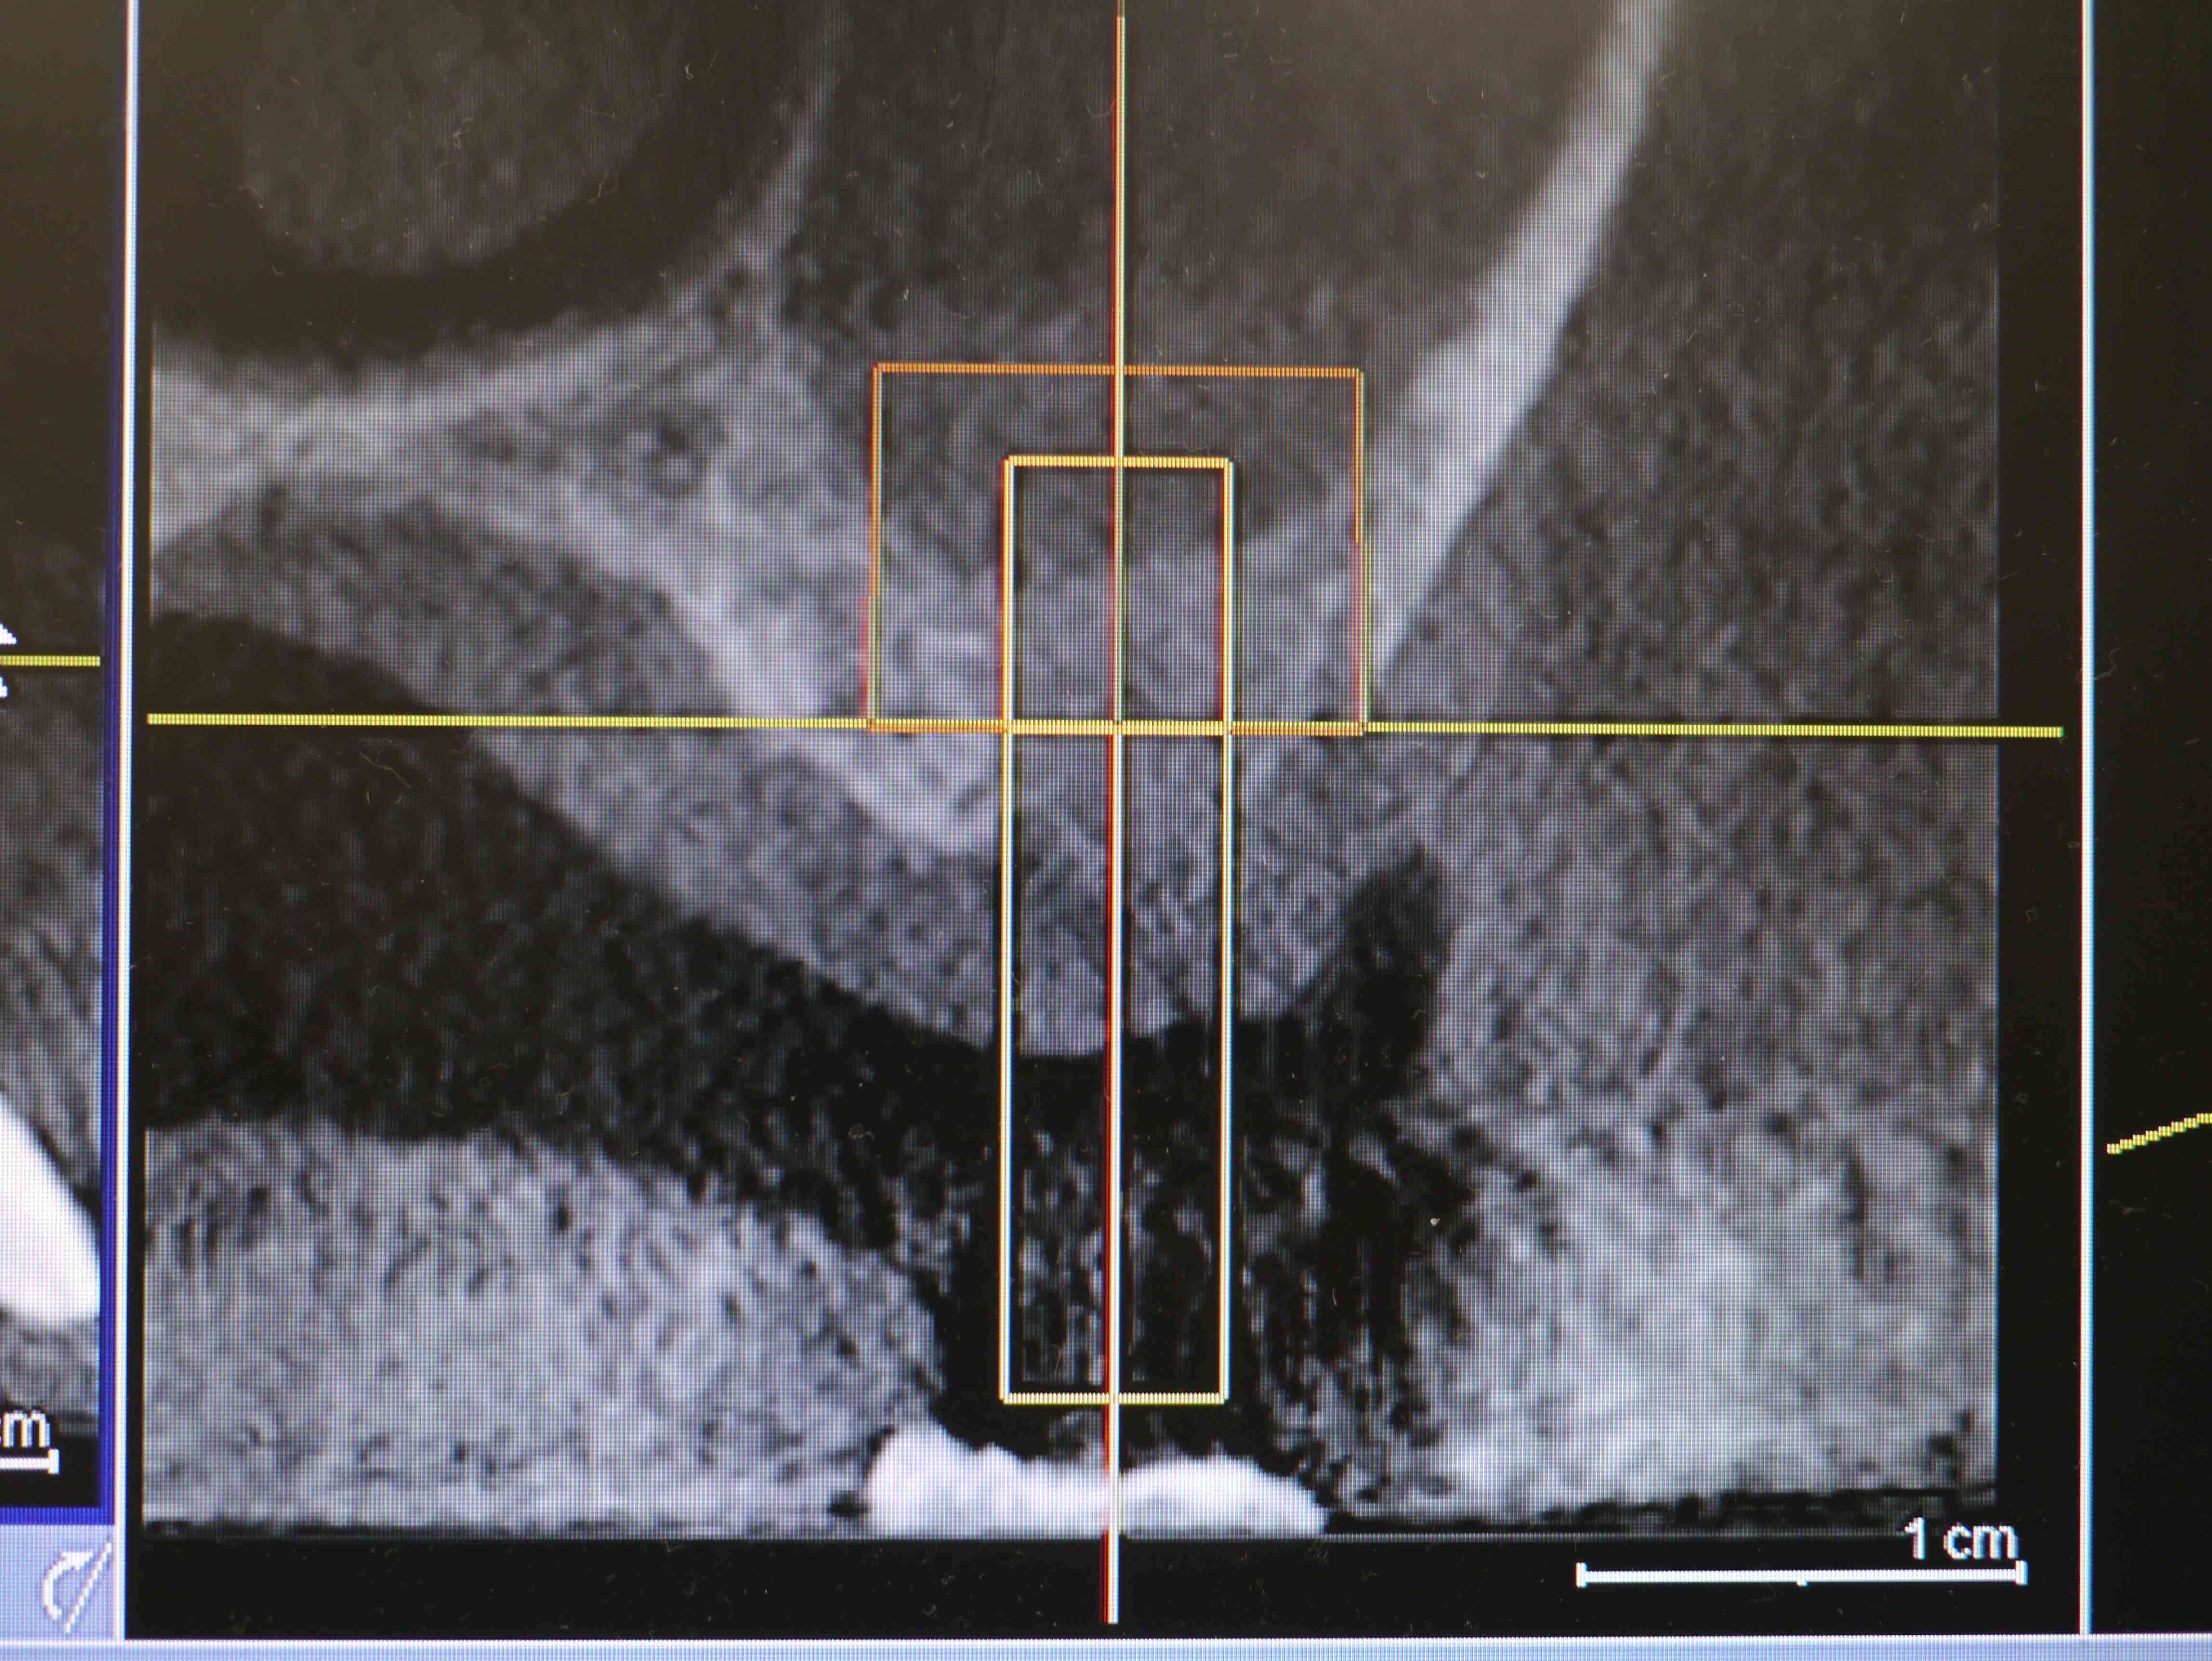

【平成26年3月26日CT画像】

CT画像4

右上7番、インプラントの先端近くまで骨が出来ている

CT画像5

右上6番、インプラントの先端まで骨が出来ている